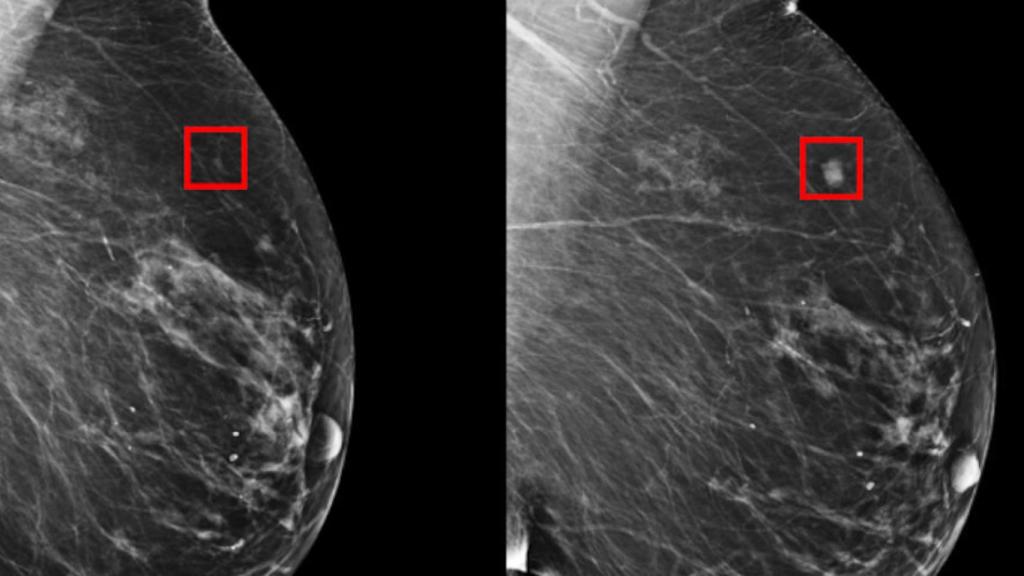

Resultados de una mamografía.